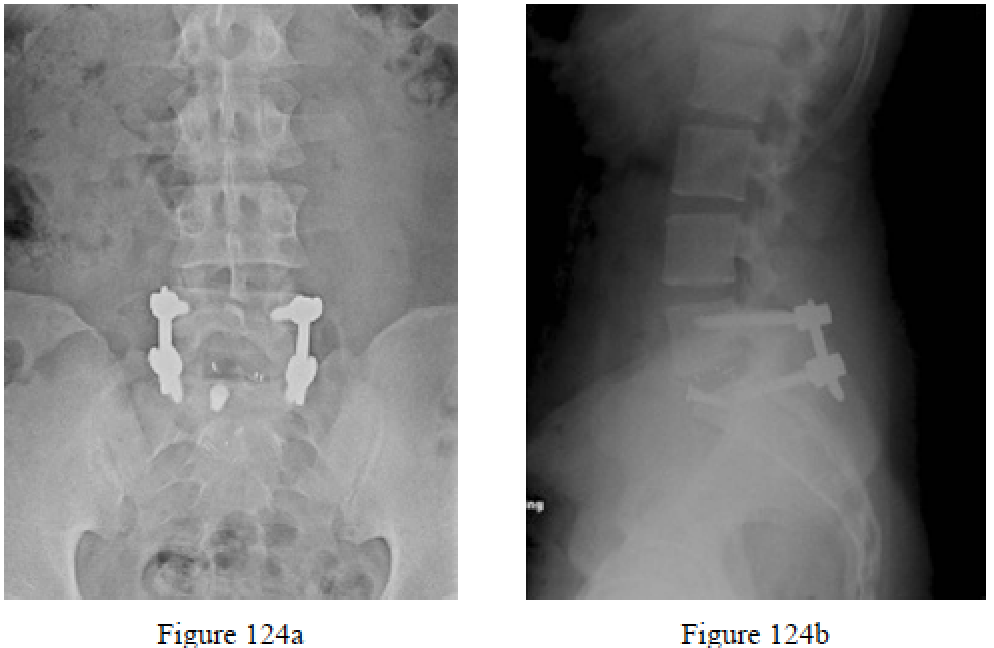

Question 124

Figures 124a and 124b are the anteroposterior and lateral radiographs of a 27-year-old man who was treated with an anterior/posterior fusion for chronic low-back pain secondary to L5 spondylolysis with spondylolisthesis. The patietn experienced difficulty with fertility after his surgery. This condition most likely was caused by an injury to which structure?